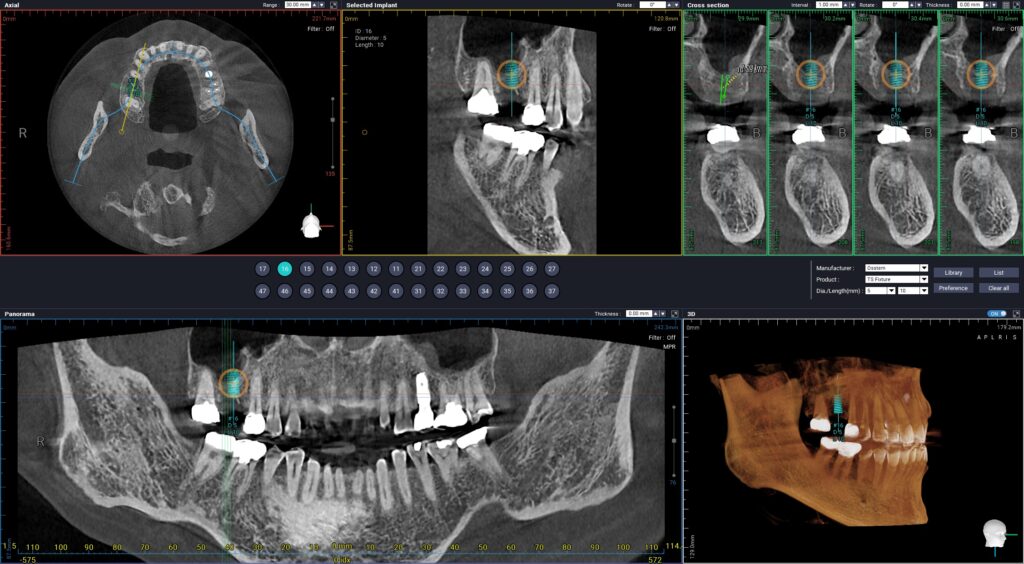

상악동의 치조정 방향에서 거상시켜

적절한 임플란트의 길이와 뼈를 만들어 주어

수술에서는 절개하지 않고 무절개 수술법을

이용했기 때문에 수술이 빠르고

통증 없이 마무리 하였습니다.

반드시 3D CT 촬영을 통해

치조골의 폭과 높이, 신경의 위치를

입체적으로 분석하는 과정이 선행되어야 합니다.